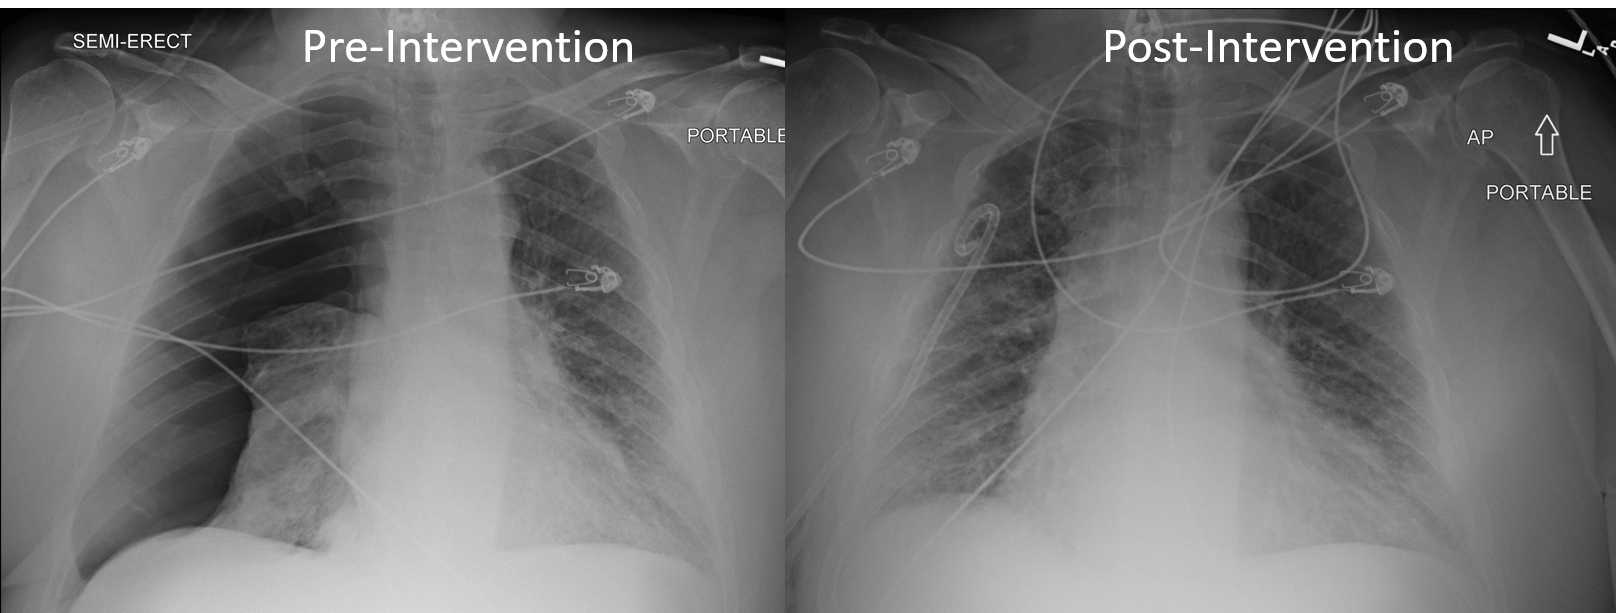

Radiology Case Shortness of Breath [clinical] r/medicalschool Shortness Of Breath Lab Diagnosis Dyspnea, also known as shortness of breath or breathlessness, is a subjective sensation of breathing discomfort. It can be caused by. Luckily, most causes of shortness of breath can be treated quickly, if not completely eliminated, once the cause is identified. Shortness of breath or dyspnea is a common symptom. Cyanosis, wheezing, diminished breath sounds, and distant heart sounds are. Shortness Of Breath Lab Diagnosis.